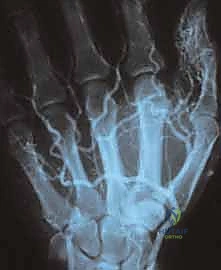

لفهم خطورة وتعقيد أورام اليد الوعائية، يجب أولاً أن نفهم التشريح المعقد لليد. اليد مساحة جغرافية صغيرة جداً في الجسم، لكنها تزدحم بهياكل حيوية لا حصر لها. التروية الدموية لليد تأتي بشكل أساسي عبر الشريانين الكعبري (Radial Artery) والزندي (Ulnar Artery)، اللذين يتحدان في راحة اليد لتكوين الأقواس الراحية (Palmar Arches)، ومنها تتفرع الشرايين الدقيقة لتغذي الأصابع.

هو المعيار الذهبي (Gold Standard) لتشخيص أورام اليد الوعائية. يوفر صوراً ثلاثية الأبعاد وعالية الدقة توضح امتداد الورم، وعلاقته بالأعصاب والأوتار والعظام المحيطة.

| الأشعة السينية (X-ray) | كشف تأثر العظام أو وجود حصوات وريدية | إذا كان هناك اشتباه بتآكل عظمي | ممتازة للعظام، ضعيفة للأنسجة |